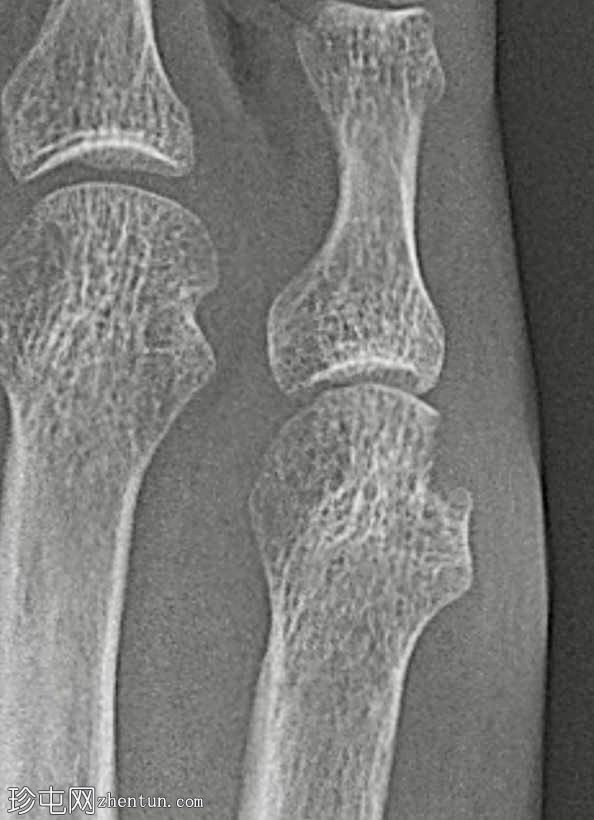

多发性

2.jpg

骨质疏松伴皮质变薄

左侧和右侧第五跖骨头关节旁骨侵蚀

边界不清

放大锐化图像